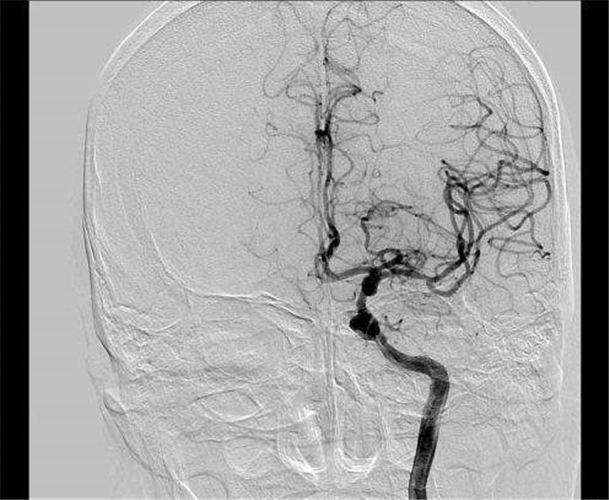

左頸內動脈狹窄導致腦供血不足